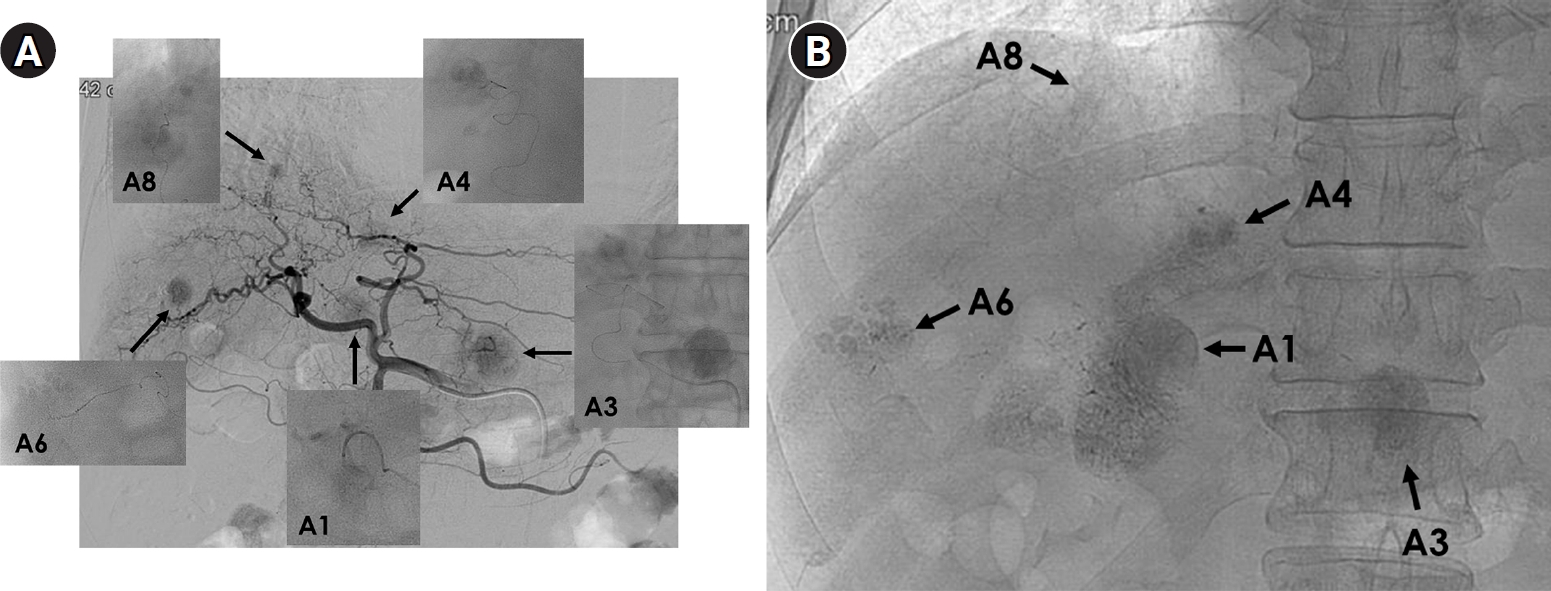

Fig. 4.

Superselective transarterial chemoembolization (TACE) for five nodular tumors in a 60-year-old man. (A) Common hepatic arteriography shows five nodular tumors. Superselective TACE was performed through tumor-feeding arteries including A1, A3, A4, A6, and A8. (B) Post-TACE fluoroscopy shows dense lipiodol uptake within the tumors without significant parenchymal deposition.

Conversely, TACE remains the backbone of transarterial therapy due to its broad applicability, repeatability, and controllability. It can be safely performed in a wide range of clinical settings as long as hepatic function is preserved. The National Cancer Center–Korean Liver Cancer Association guidelines continue to recommend TACE as the best or alternative treatment option across most stages of HCCs, underscoring its versatility and reliability [5]. Moreover, the ability to visualize lipiodol-based emulsions under fluoroscopy allows for real-time monitoring and precise control, enabling superselective embolization that maximizes tumor necrosis while sparing functional parenchyma [14] (Fig. 4). There is a report that superselective TACE yielded survival outcomes similar with early HCC for patients beyond Milan but within up-to-seven criteria [33]. Korean interventional radiologists, in particular, have achieved remarkable tumor control through refined superselective techniques, even in anatomically complex or high-risk cases where other modalities may not be feasible. The technical sophistication developed in East Asia, especially in Korea and Japan, has produced outcomes that often exceed those reported in Western studies [6]. Using meticulous microcatheter techniques, embolization can be performed safely even in patients with marginal hepatic reserve or tumors near critical structures, minimizing non-target injury while maintaining high tumor response rates. In Korea, TACE is not only technically advanced but also widely accessible and cost-effective, supported by a national insurance system that enables most tertiary and regional hospitals to perform the procedure. In my opinion, perhaps half in jest, no other country can offer such highly selective TACE at such an affordable cost, which reflects both the skill of Korean interventional radiologists and the efficiency of the healthcare system.